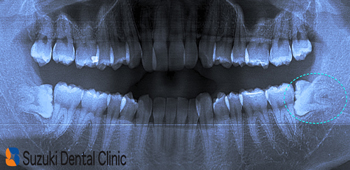

コラム「横向きの親知らず」の画像